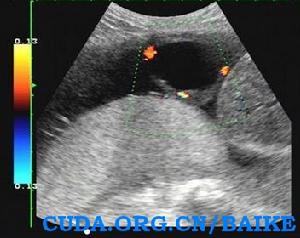

臍帶囊腫1、臍帶內部可見圓形無回聲結節,包膜完整,內部透聲好。 2、CDFI示囊腫內部無血流信號。

3、局部臍帶血管可能有受壓改變。

4、詳細系統檢查有無胎兒結構畸形。